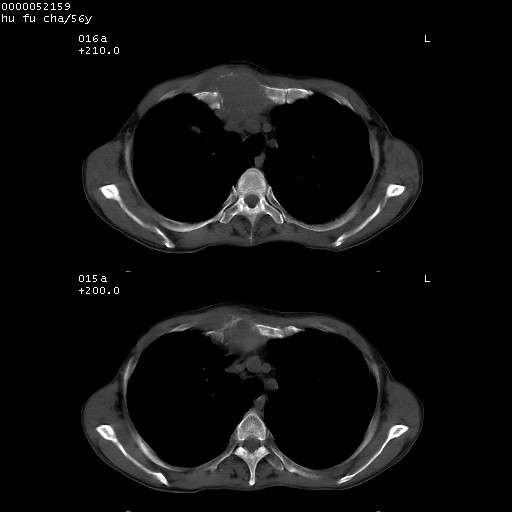

以下是引用zsl6918在2008-8-25 22:47:00的发言:[br]胸骨,胸椎及肋骨均可见多发转移表现,肝内低密度结节不除外转移。原发灶可能在右肺。双侧可见支扩表现。

以下是引用宇宙ct在2008-8-25 23:26:00的发言:[br][br] 胸骨,胸椎及肋骨均可见多发转移表现,肝内低密度结节不除外转移。原发灶可能在右肺。双侧可见支扩表现。 [br] [br]

以下是引用卜一在2008-8-26 8:02:00的发言:[br][br] 支持:肺癌并肺内,胸骨,胁骨,胸椎及肝内转移!另:左肺支气管扩张征伴感染! [br]

以下是引用zjzjr在2008-8-26 11:03:00的发言:[br]支持:肺癌并肺内,胸骨,胁骨,胸椎及肝内转移!另:左肺支气管扩张征伴感染!